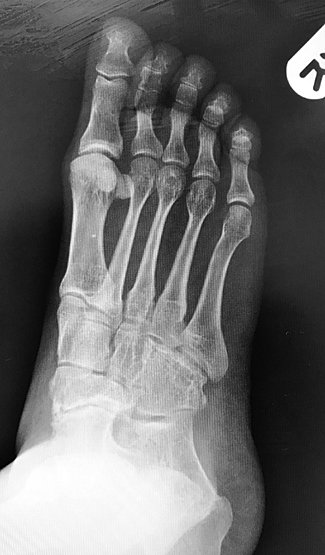

What is a talonavicular fusion? The hindfoot consists of four bones and three joints. Fishco the talonavicular joint arthrodesis is utilized for various pathologies of the foot.

Disease of cartilage leads to roughened surfaces which causes friction and increased wear and tear in the joint. This is an operation to “fuse” or stiffen a joint in the middle part of the foot. The talonavicular, talocalcaneal, and calcaneocuboid joints.

For me the talonavicular surgery has been a definite improvement. The talus, calcaneus, cuboid, and navicular bones are separated by cartilage and create the talocalcaneal, talonavicular, and calcaneocuboid joints. My talo navicular fusion was march 30.